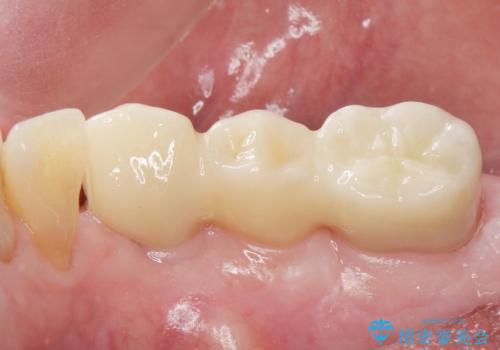

再生療法と骨外科処置により、歯周ポケットは全周2mm以下となりました。

奥歯の動揺がなくなりしっかりと咬むことができ、審美的・機能的にもご満足頂けました。

被せ物の種類:オールセラミッククラウン ベレッツァ